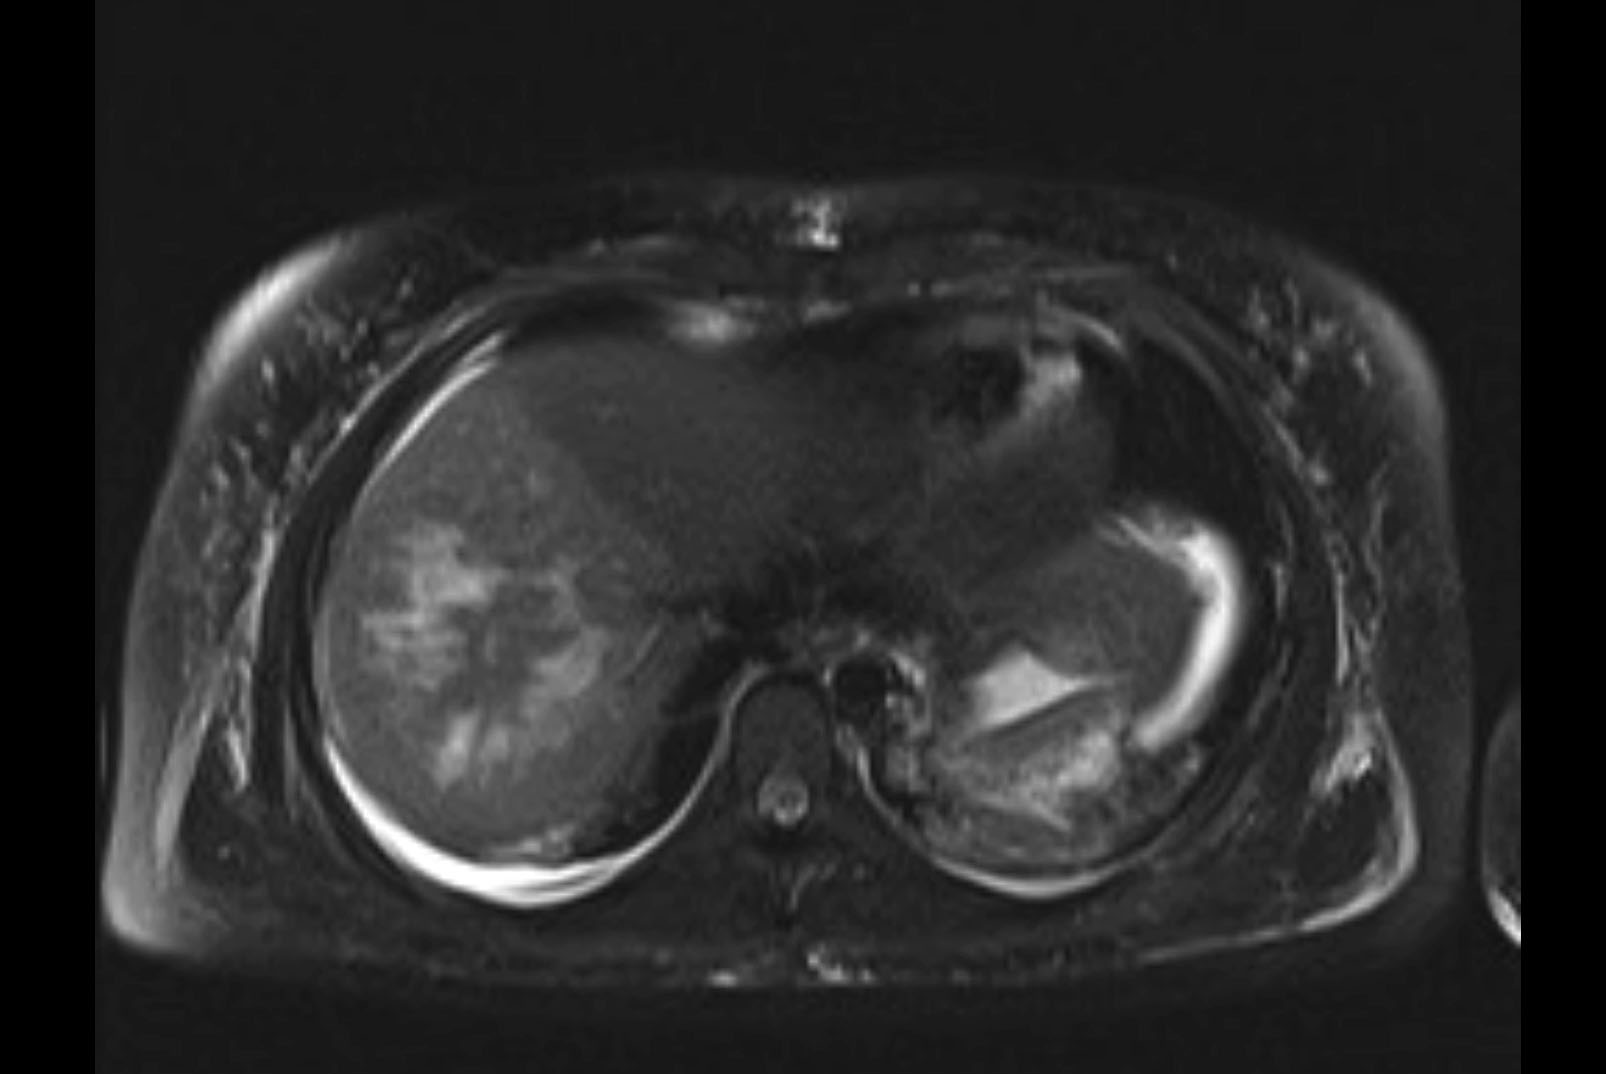

MRI T1

MRI T2